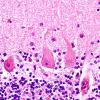

Neuronal Ceroid Lipofuscinosis (NCL) (5)